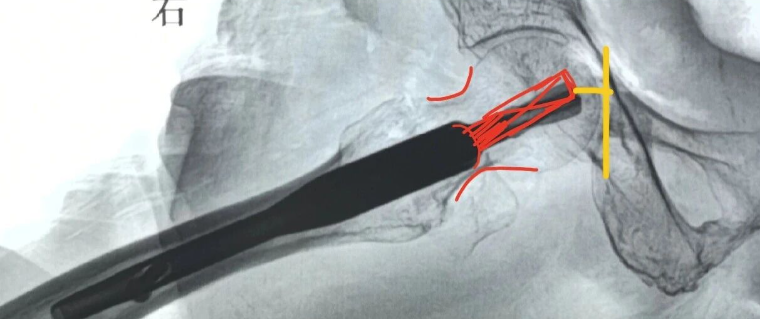

皮质类固醇注射是Morton神经瘤非手术治疗的一种选择,尽管它们可能只能提供短期的疼痛缓解。并发症不常见;大约30%的患者最终可能会在注射后继续接受手术干预。超声引导和非超声引导注射在疗效上没有差异。